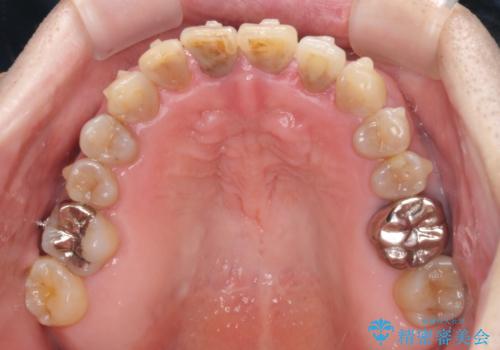

上顎の狭窄歯列 インビザラインによる拡大矯正

- 前歯の叢生と臼歯のクロスバイトを気にして来院された患者様です。

急速拡大装置による上顎の側方拡大を行い、その後はインビザラインより歯列を改善することとしました。

20代後半以降の男性は上顎骨の側方拡大処置の成功率が低く、今回も骨を拡大することができませんでした。

しかしながら、歯列を側方に拡大することができ、その後はインビザラインにて叢生を解消することができました。